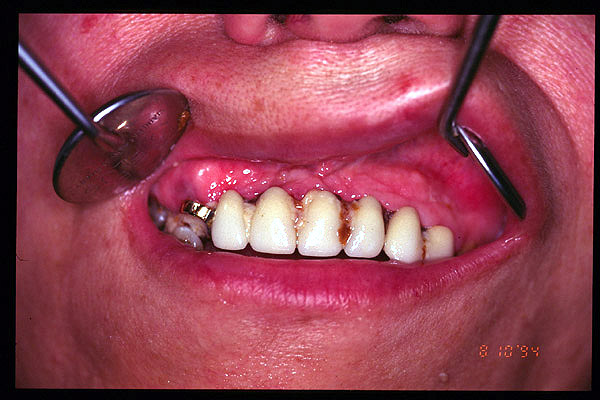

CM Enfermedad periodontal avanzada. Cálculos.